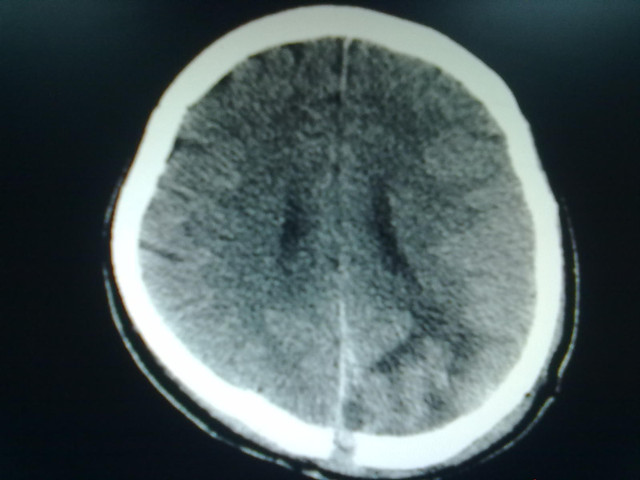

术前影像学改变

术后复查